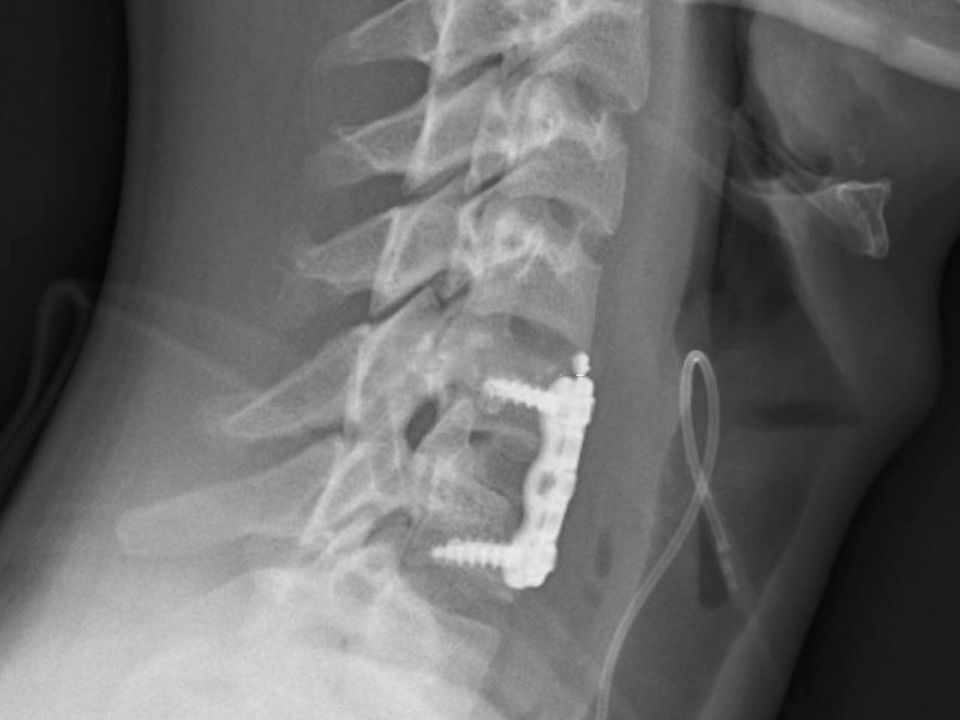

«Мы провели операцию по удалению поврежденного диска и отломка, зафиксировали позвонки пластиной», — рассказал Сергей Горчаков, заведующий отделением нейрохирургии.

Послеоперационный период прошел благополучно. Контрольный рентген подтвердил успешную установку костного аутотрансплантата и надежную фиксацию позвонков с помощью накостной пластины.